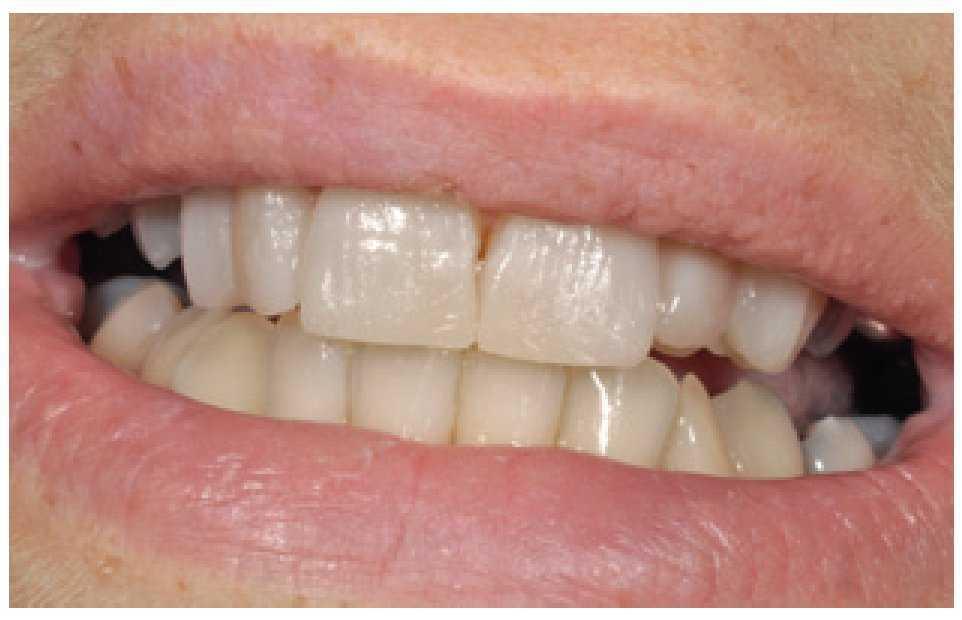

Figura 13 La sonrisa de la paciente.